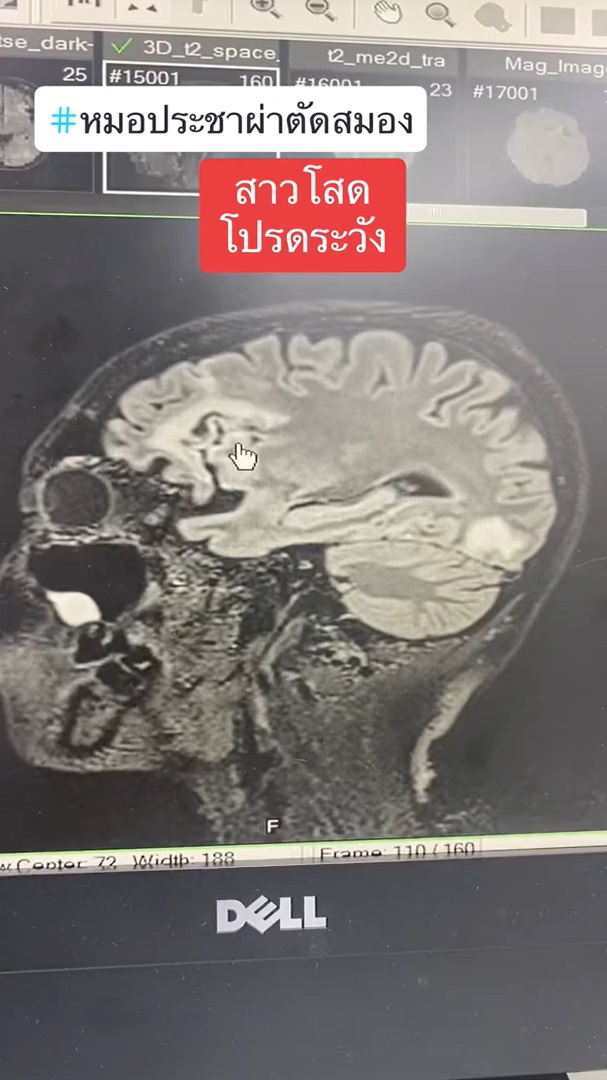

ทำเอาเหล่าสาวโสดถึงกับร้อน ๆ หนาว ๆ หลังจากที่ นายแพทย์ประชา กัญญาประสิทธิ์ หมอผ่าตัดสมอง ออกมาโพสต์เตือนภัยใกล้ตัวที่มีแนวโน้มจะเกิดกับสาวโสดได้ง่ายกว่าคนที่มีลูก โดยได้ยกเคสผ่าตัดเคสหนึ่งมาเป็นกรณีศึกษา ระบุว่า มีผู้ป่วยหญิง อายุ 57 ปี เป็นสาวโสดอยู่คนเดียว มาหาหมอด้วยอาการพูดจาสับสน ซึ่งผลการตรวจเอกซเรย์ พบว่า มีสมองตายหลายจุด ตายทั้งข้างหน้า ข้างหลัง ลามไปจนถึงท้ายทอย ทำให้ตามัว และมีจุดเลือดออกในหย่อมที่สมองตายด้วย และยังตรวจพบอีกหลายอย่าง อาทิ

แคลเซียมก็สูงมาก จากลักษณะของมะเร็ง ไม่ใช่กระจายไปที่สมอง ลิ่มเลือดอุดตันที่ขาสองข้าง ทำให้ขาบวม ทั้งยังเกิดลิ่มเลือดอุดตันในสมองหลายตำแหน่ง คนไข้จึงมาด้วยอาการพูดจาสับสน สุดท้ายกลายเป็นมะเร็งรังไข่ ซึ่งเคสนี้ก็ต้องผ่าตัดและสู้กับมะเร็งรังไข่กันต่อไป